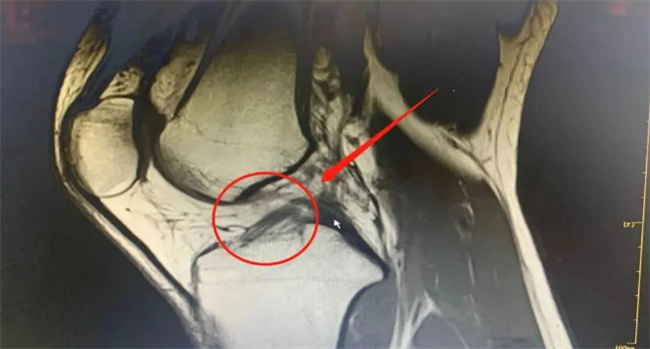

韌帶斷裂會(huì)有腫脹疼痛,局部血瘀,肌肉痙攣以及關(guān)節(jié)活動(dòng)受到限制等等。一般在行走過(guò)程中就會(huì)感覺(jué)到有劇烈的疼痛,甚至關(guān)節(jié)部位也沒(méi)有辦法正常的轉(zhuǎn)動(dòng),因此還是需要注重一些細(xì)節(jié)。

根據(jù)分析,韌帶一旦出現(xiàn)斷裂就有明顯的腫脹以及疼痛現(xiàn)象,比如在轉(zhuǎn)動(dòng)關(guān)節(jié)還有行走時(shí),就會(huì)發(fā)現(xiàn)嚴(yán)重的疼痛加重。一旦發(fā)生韌帶斷裂在斷裂的部位,還會(huì)有明顯的積血現(xiàn)象,甚至局部還會(huì)出現(xiàn)嚴(yán)重的血瘀。一般在選擇按摩之后,血瘀的情況或許就會(huì)變得更加的明顯。這一類的癥狀可能就會(huì)持續(xù)較長(zhǎng)的一段時(shí)間,因此也需要注重于每一個(gè)細(xì)節(jié)。

在正常的情況下,韌帶的邊上就會(huì)連接肌肉連接骨骼,在日常生活中一個(gè)不小心導(dǎo)致斷裂,相應(yīng)的肌肉組織自然也沒(méi)有辦法獲得更好的保護(hù),因此就容易會(huì)形成肌肉痙攣。在運(yùn)動(dòng)過(guò)程中方法不正確或者劇烈的運(yùn)動(dòng),一旦發(fā)現(xiàn)下肢出現(xiàn)痙攣,一定要引起重視,因?yàn)檫@很有可能就是韌帶斷裂所造成的。

還有一部分人在出現(xiàn)韌帶斷裂之后,會(huì)導(dǎo)致關(guān)節(jié)的正常活動(dòng),受到相應(yīng)的限制,會(huì)出現(xiàn)明顯的關(guān)節(jié)活動(dòng)障礙。比如有一部分人會(huì)發(fā)現(xiàn),在行走的時(shí)候疼痛就會(huì)明顯的加劇,還會(huì)有關(guān)節(jié)轉(zhuǎn)動(dòng)不力以及關(guān)節(jié)屈伸不力等現(xiàn)象。在這一個(gè)階段不建議隨意的運(yùn)動(dòng),此時(shí)無(wú)論是選擇按摩還是選擇運(yùn)動(dòng)會(huì),導(dǎo)致斷裂的現(xiàn)象變得更加嚴(yán)重,一定要及時(shí)到醫(yī)院接受治療。當(dāng)前在治療時(shí)主要的方法是通過(guò)固定情況嚴(yán)重還需要接受手術(shù)治療。